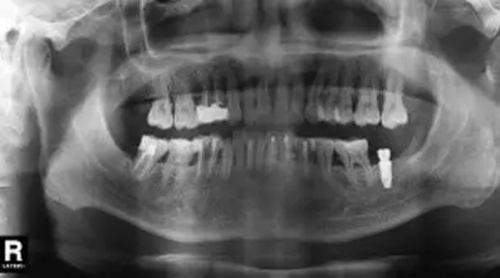

臨床檢查46面見大面積銀汞充填物,近中頰側(cè)部分牙體折裂至齦下約2mm,折裂部分已與牙體分離。46叩痛(-),松動度(-),牙齦(-),未探及牙周袋形成。曲面體層片示46髓腔內(nèi)及根管見高密度影像,未至根尖,根尖未見明顯陰影(圖1)。

圖1 拔牙術(shù)前曲面體層片 診斷46折裂牙(死髓牙)。